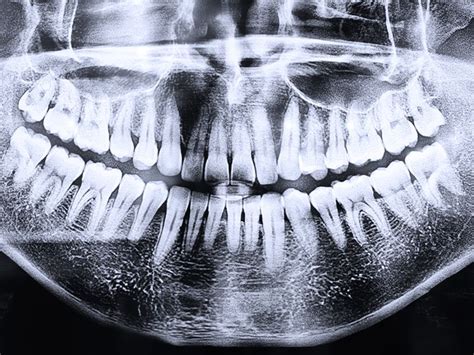

- Exploración radiográfica: Utilización de diversas técnicas radiográficas para evaluar la estructura ósea y la posición de los implantes:

- Rx panorámica